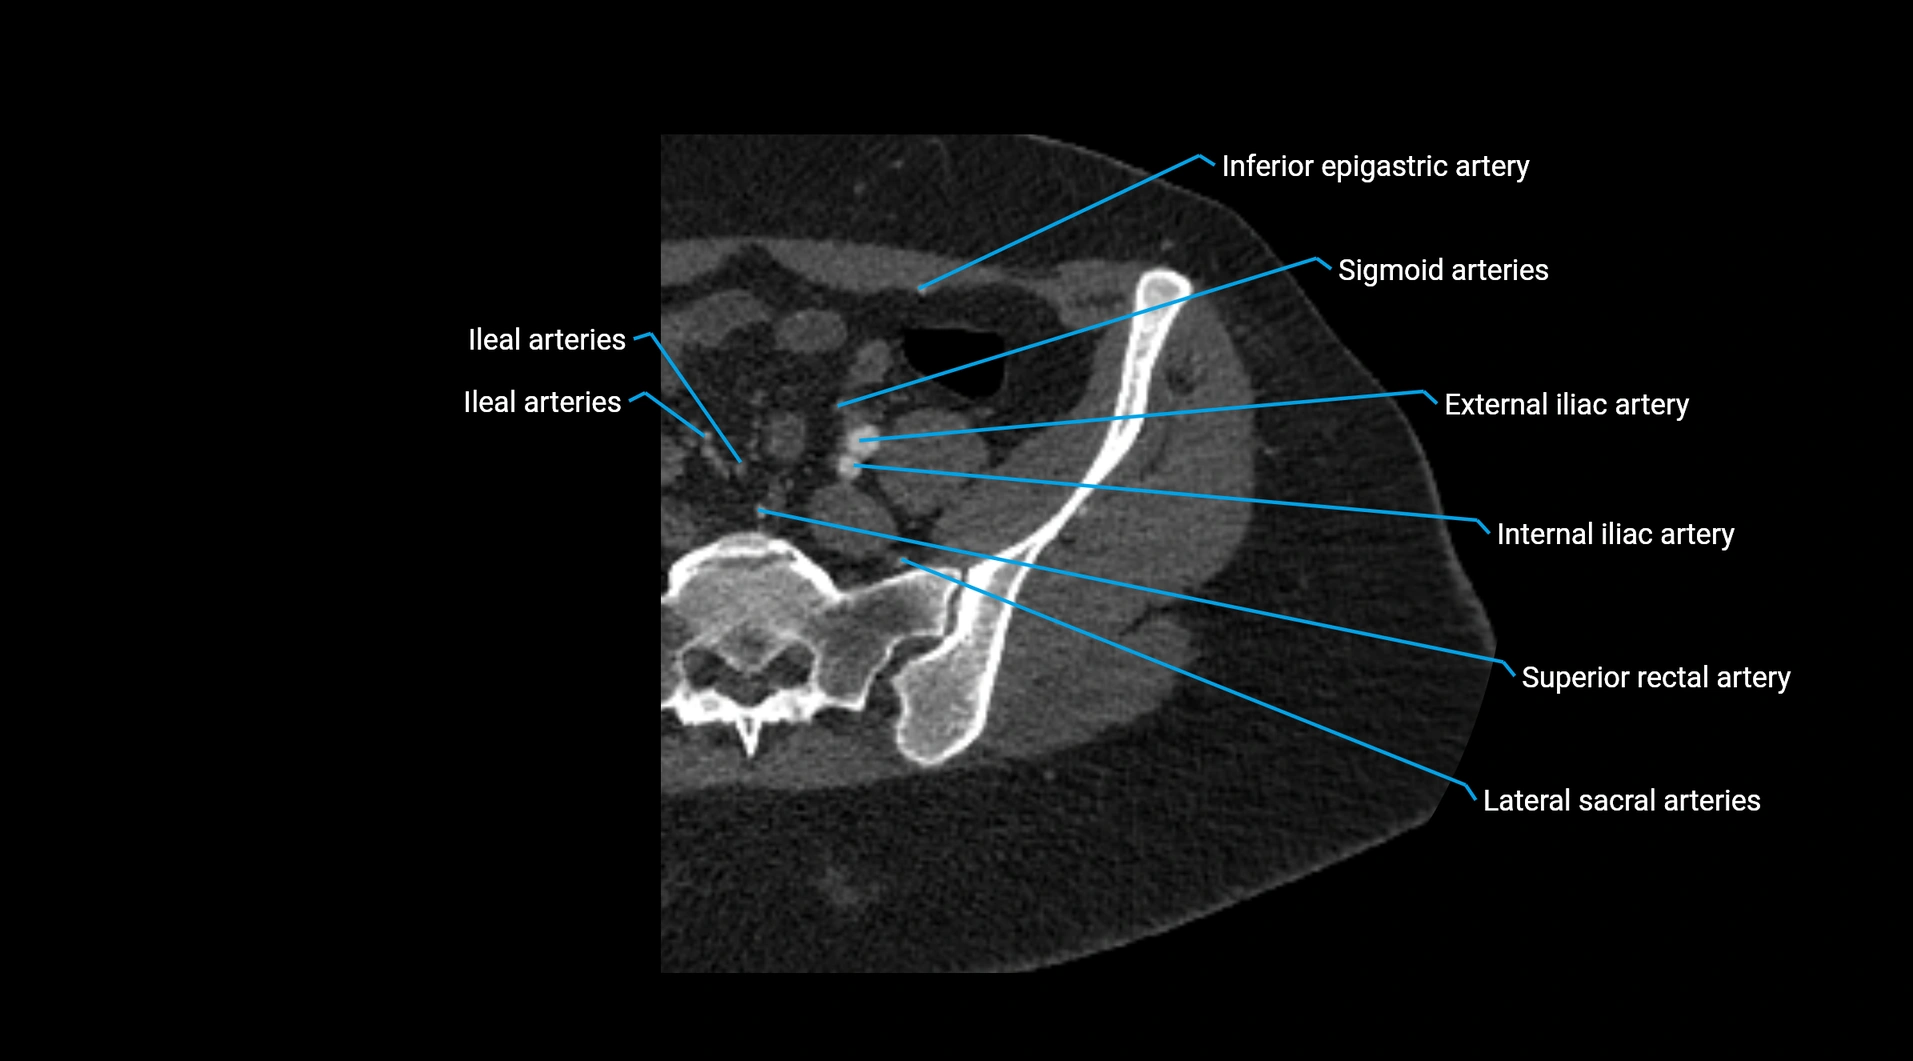

Contrast-enhanced CT (CTA):

• Gold standard for abdominal aortic imaging

• Provides excellent detail of lumen, wall, aneurysm, thrombus, and branch vessels

• Multiplanar and 3D reconstructions help in aneurysm measurement, stent graft planning, and dissection evaluation

• Unpaired visceral branches: celiac trunk, superior mesenteric artery (SMA), inferior mesenteric artery (IMA)

• Paired visceral branches: middle suprarenal arteries, renal arteries, gonadal arteries (testicular or ovarian)

• Parietal branches: inferior phrenic arteries, lumbar arteries, median sacral artery

• Terminal branches: right and left common iliac arteries